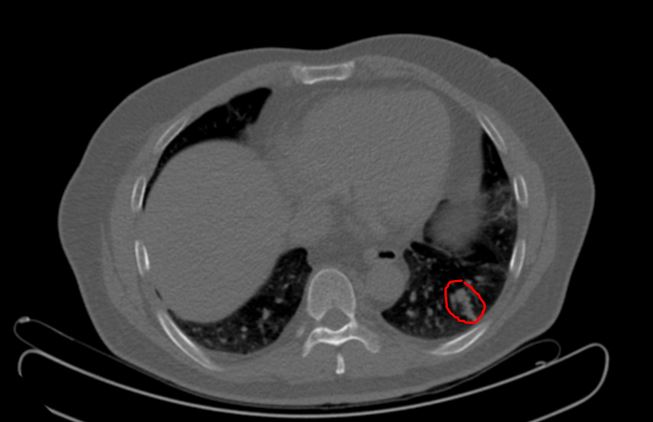

到达美国Edge治疗中心(亨利福特)后PET-CT检查:排除右肺肿块肿瘤可能;左肺出现3个肿块,如下图。

8月15日结束治疗后回国。2015年10月14日在中国当地医院复查,何先生情况良好,胸部CT显示肺部肿块肿瘤灶消失、纤维化,见治疗前后影像图(左图为治疗前,右图为治疗后2月)。